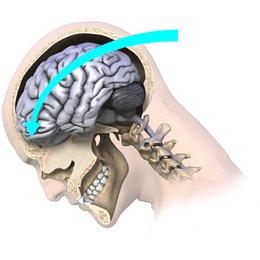

The brain is the body’s control center. Certain types of injuries are known to cause damage to the brain and engaging in such sports activities especially contact sports, tend to increase the risk of injuring the brain. Events such as car accidents or falls can also lead to brain injury. A concussion is the term that is commonly used for a mild to moderate traumatic brain injury, but this health problem is often overlooked.